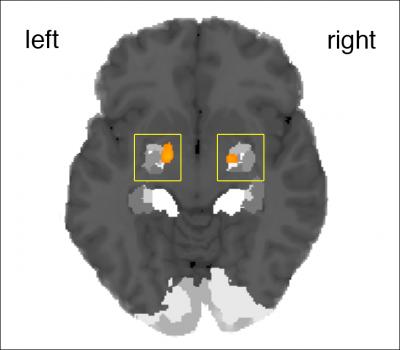

"Musical improvisations are more variable in their loudness and timing, most likely due to irregularities in force control associated with fluctuations in certainty about upcoming actions—i.e., when spontaneously deciding what to play—during improvised musical performance", explains Peter Keller. The amygdala, part of the limbic system, was more active while listening to real improvisations and was sensitive to the fluctuations of loudness and timing in the melodies. Thus, the amygdala seems to be involved in the detection of spontaneous behaviour, which is consistent with studies showing an involvement of this structure when stimuli are difficult to predict, novel or ambiguous in their meaning.

If a melody was judged as being improvised, regardless of whether this was in fact the case, stronger activity was found in a network which is known to be involved in the covert simulation of actions. This network comprised the frontal operculum, the pre-supplementary area and the anterior insula.